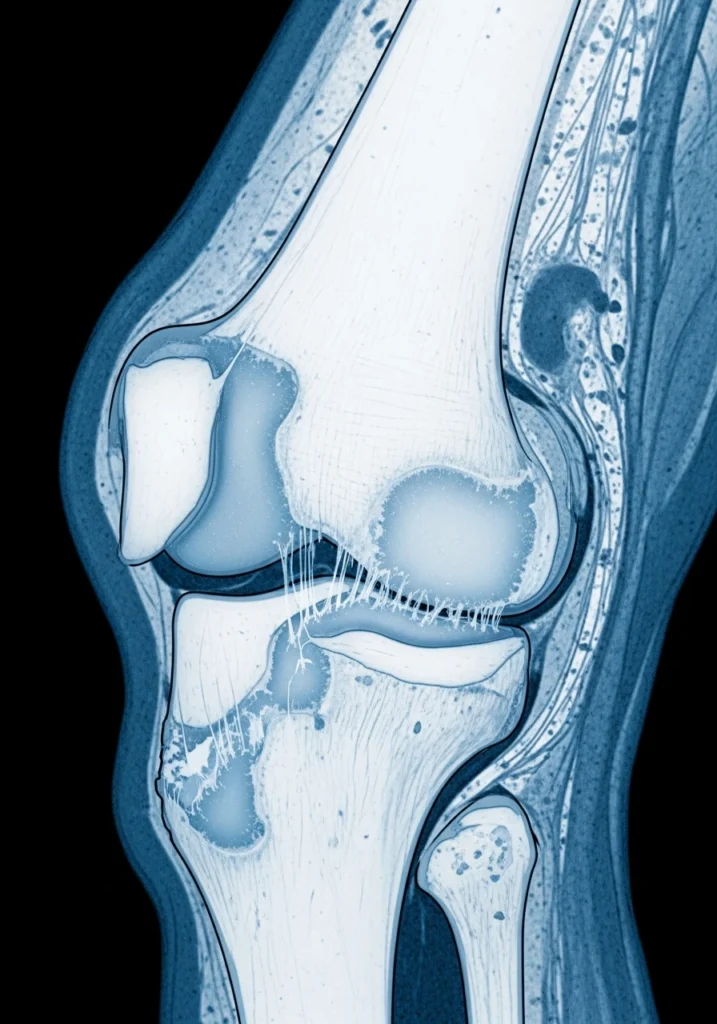

Резекция мениска — одна из самых частых ортопедических операций. Хотя она быстро устраняет боль, она увеличивает риск артроза коленного сустава в дальнейшем.

Это связано с тем, что мениск — главный амортизатор колена. После его частичного удаления нагрузка на хрящ увеличивается, а метаболизм синовиальной жидкости изменяется.

Эти изменения могут начинаться уже через 6–12 месяцев после операции.